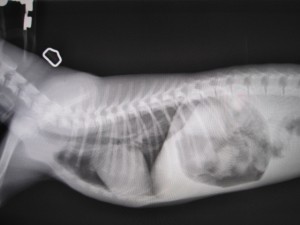

術後

術後のレントゲンです。

食道内異物はなくなりました。